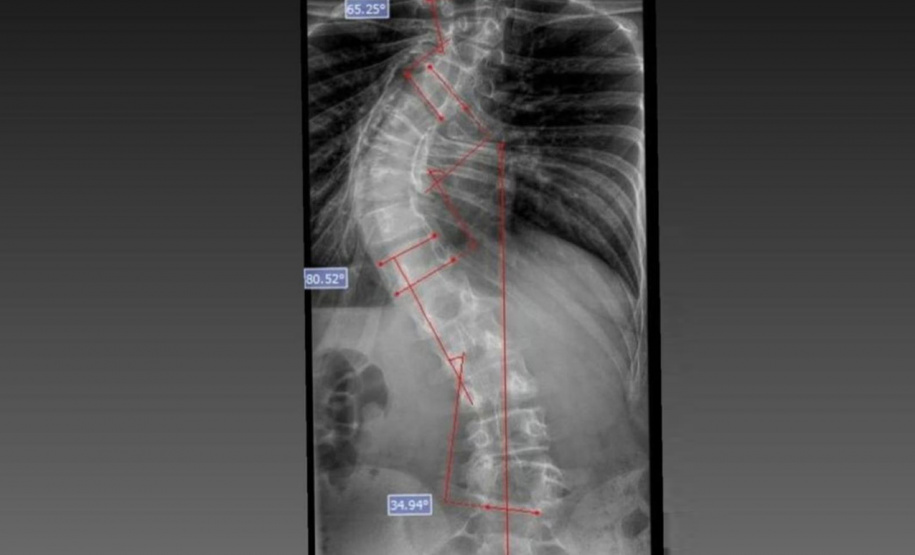

Laura era portadora de escoliose e, em agosto de 2025, realizou a cirurgia de correção da coluna, o que lhe permitirá ter uma vida normal de agora em diante. Moradora de Bom Sucesso do Sul, região Oeste do Paraná, é acostumada a andar a cavalo, mas com o problema na coluna a prática estava longe de ser prazerosa.

DIAGNÓSTICO - A escoliose pode ter diferentes causas, sendo classificada em idiopática (sem causa definida), sindrômica (associadas a síndromes genéticas), neuromuscular (decorrente de doenças como paralisia cerebral e atrofia muscular espinhal) e congênita (presente desde o nascimento). Em todos os casos, o diagnóstico precoce e o acompanhamento especializado são fundamentais para determinar a melhor abordagem terapêutica.

O médico João Elias explica que a escoliose é um termo usado para quando você olha a coluna e percebe uma curvatura. Pode acontecer por várias causas, desde uma escoliose congênita, quando o bebê nasce com uma vértebra mal formada e essa vértebra vai levando ao desenvolvimento de uma deformidade na coluna; a neuromuscular, causadas por doenças neurológicas ou musculares, como uma paralisia cerebral, até as idiopáticas, causadas por alterações genéticas e que podem se desenvolver apenas na adolescência.

Segundo ele, o verão é o período em que mais se diagnostica a doença. Por causa do uso de roupas mais leves, é mais fácil notar a alteração na coluna. Caso seja percebida alguma alteração, uma avaliação ortopédica deve ser marcada. “O diagnóstico precoce é importante. Quando a gente percebe que a coluna está iniciando uma curvatura é possível controlar essa curva. Fazer o procedimento com uma curvatura menor permite melhores resultados na cirurgia”, explicou.